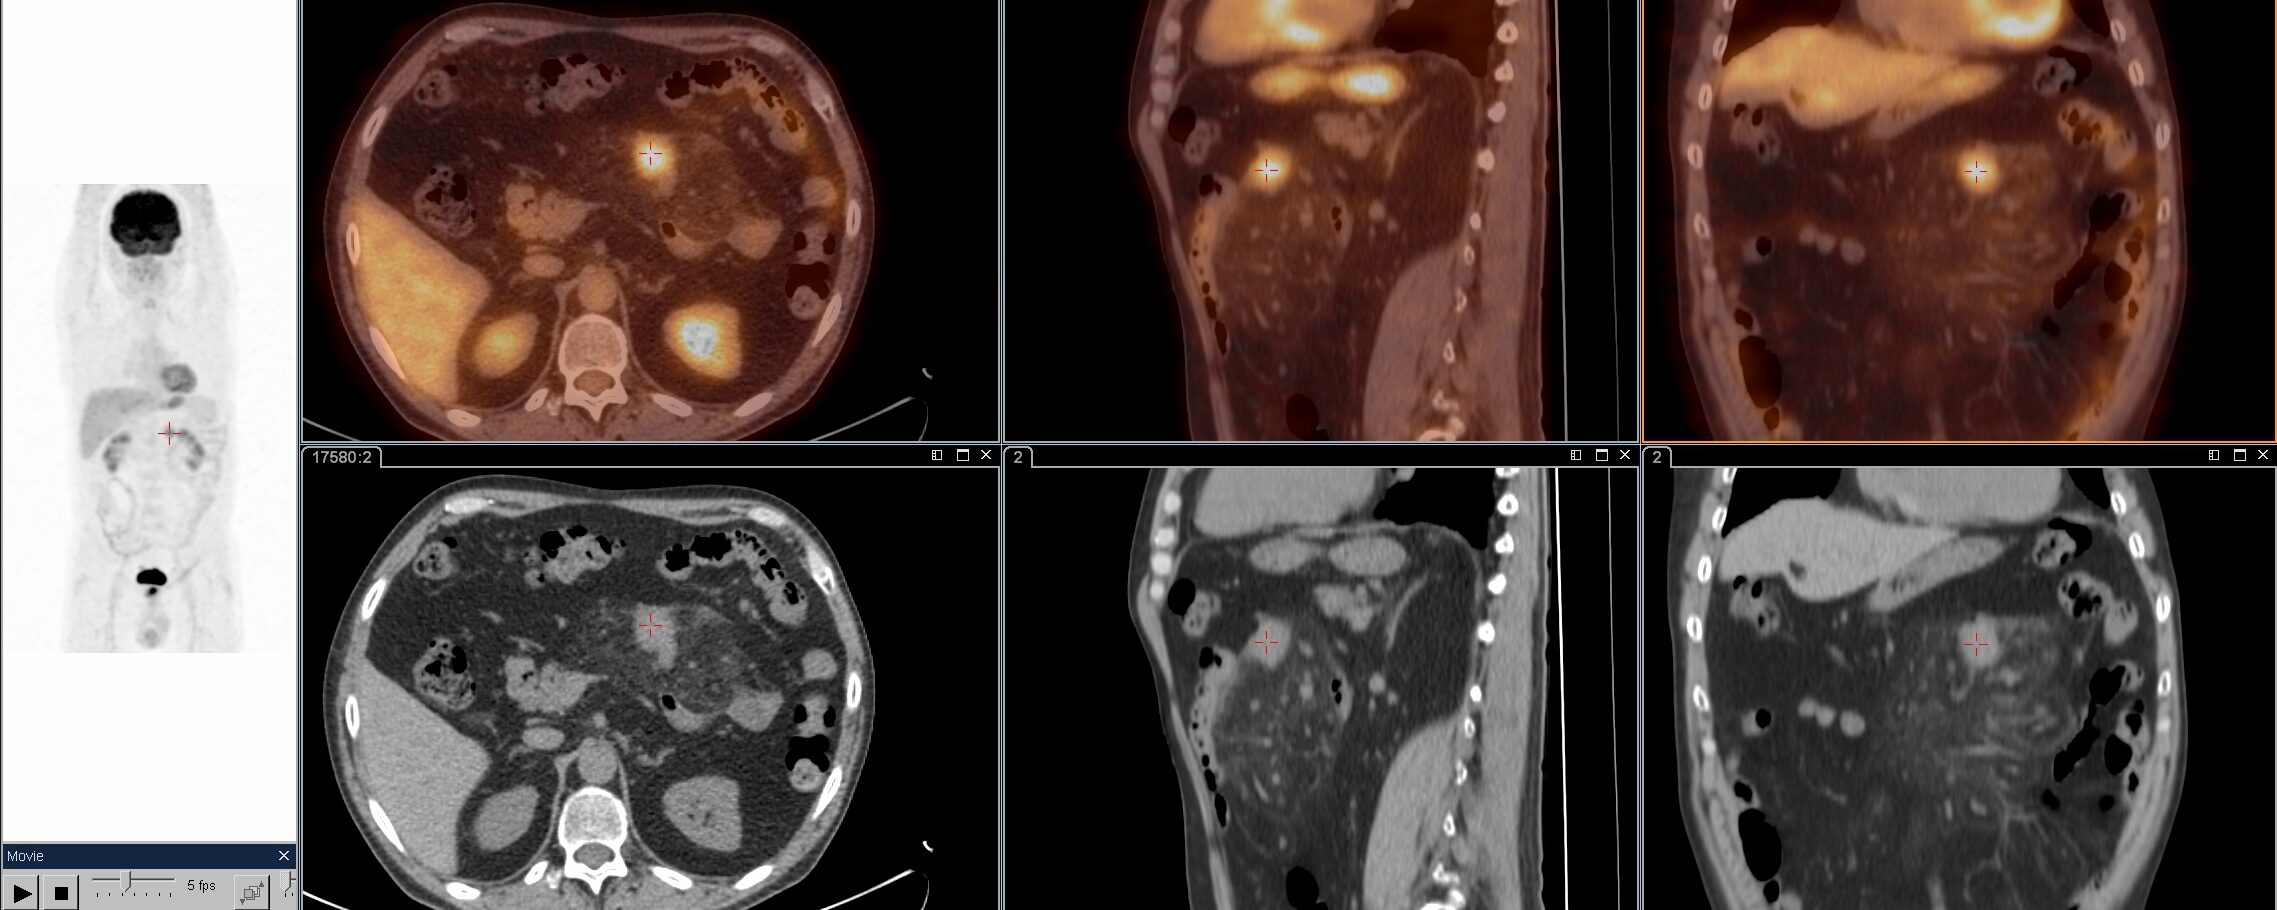

Patiente de 58 ans présentant une altération de l’état général avec fièvre et perte de poids récente.

Une TEP FDG est réalisée dans le bilan diagnostique initial.

Présence inhabituelle d’adénomégalies nécessitant des investigations complémentaires par TEP-SCAN